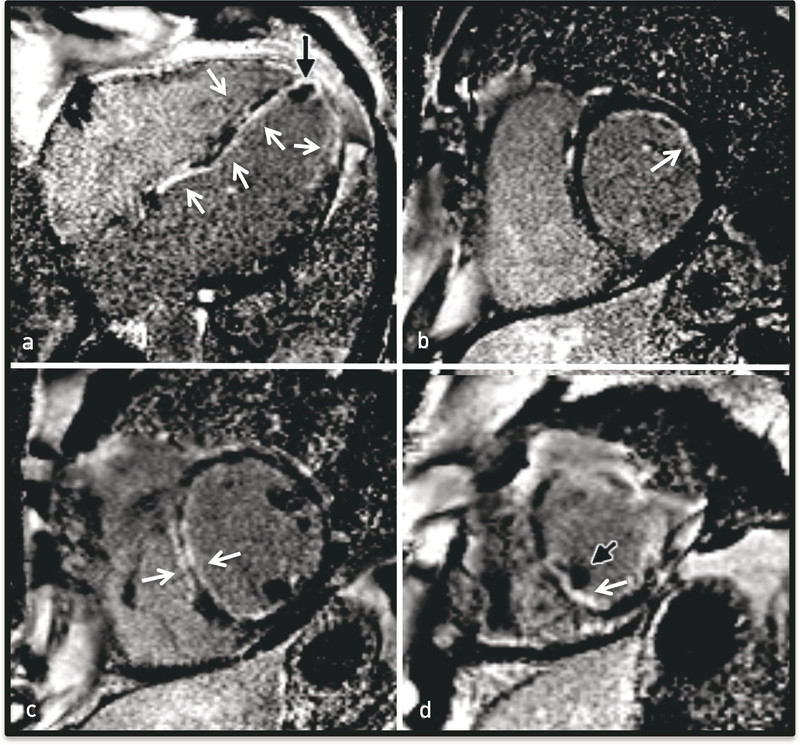

Bildet var mest forenlig med hjertesvikt med lungestuvning og eventuelt infeksjon. Konsolideringer i underlappene kan være forenlig med eosinofile infiltrater, men er ikke spesifikke for dette. CT av bihulene viste betydelige slimhinnefortykkelser i alle bihuler. MR cor viste dilatert venstre ventrikkel med et endediastolisk volum på 319 ml (normalt 65 – 240 ml) og en ejeksjonsfraksjon på 20 %.

Det ble sett en mindre apikal trombe og omfattende subendokardialt forsinket kontrastopptak etter 10 – 12 minutter som uttrykk for fibrose/nekrose, godt forenlig med iskemi forårsaket av vaskulitt i små kar (e-fig 4, video 2). Dagen etter ble det tatt endomyokardial biopsi. I påvente av biopsisvaret ble det startet, på klinisk, biokjemisk og radiologisk mistanke, behandling for eosinofil granulomatose med polyangiitt.